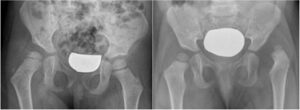

(a) Displasia dell’anca destra: la testa del femore è correttamente centrata, ma l’inclinazione dell’acetabolo (indice acetabolare) è più verticale; (b) lussazione anca sinistra.